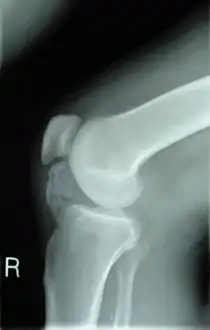

![]() Lateral radiograph of the knee demonstrating ossification in the peritendinous tissues in a patient with osteochondroma. Lateral radiograph of the knee demonstrating ossification in the peritendinous tissues in a patient with osteochondroma. | |